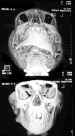

El protocolo típico de TC orbitaria (figuras 1 y 2) consiste en cortes contiguos de 3 cada 3 mm paralelos a la línea infraorbitomeatal (7). Algunos autores recomiendan realizar estudios de alta resolución con cortes finos de 1,5 mm para detectar el tumor con mayor seguridad (1).

25-01.jpg (15193 bytes)

Figuras 1a y b. Retinoblastoma: 2 casos estudiados en TC. Buena delimitación del componente cálcico con TC axial en 2 casos de RTB .

25-02.jpg (14688 bytes)

Figura 2. Reconstrucción tridimensional craneofacial para una mejor valoración de asimetrías.